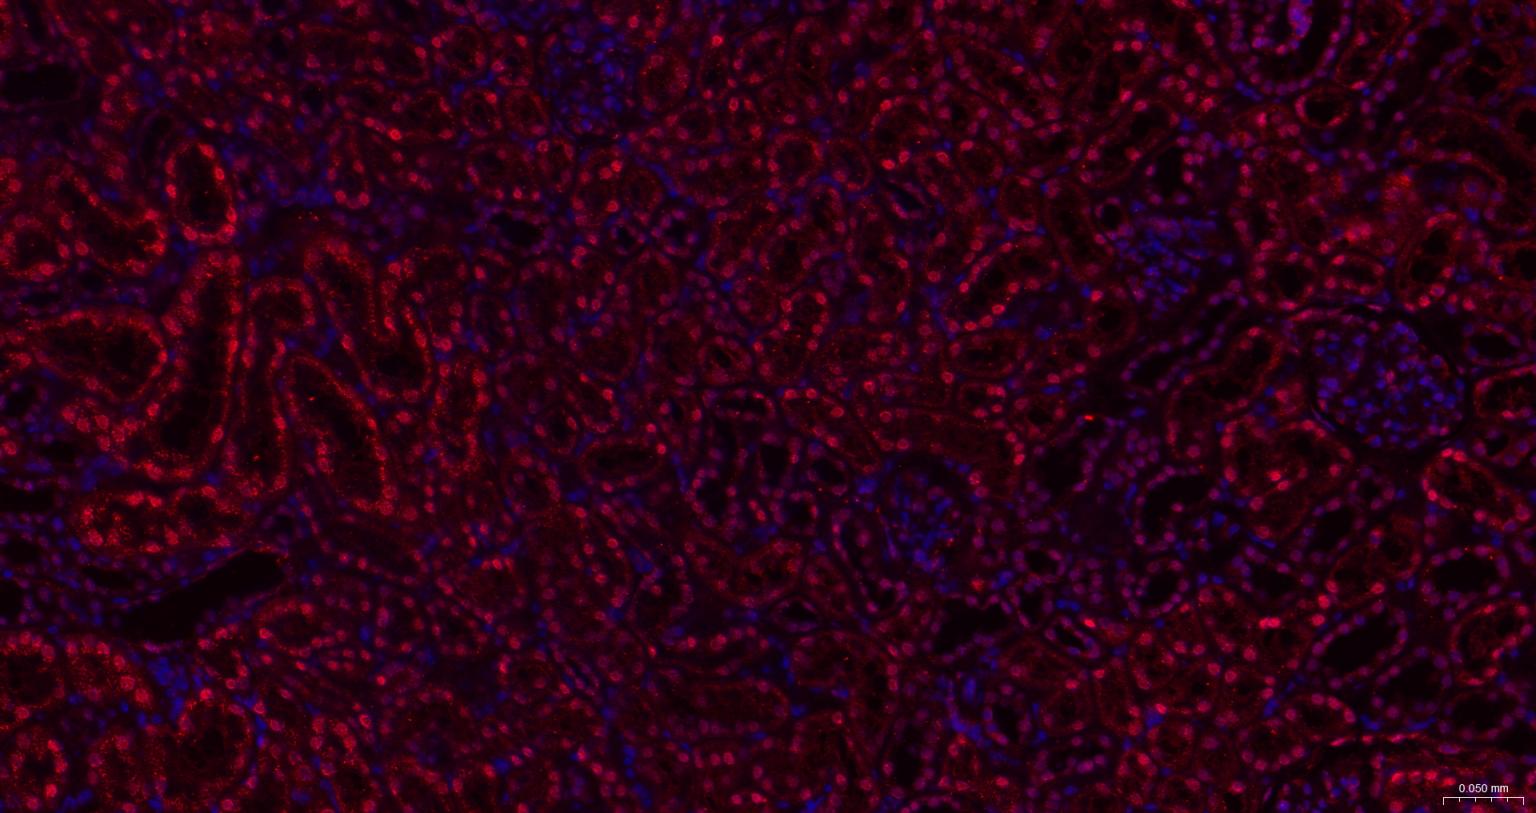

Paraformaldehyde-fixed, paraffin embedded Human Placenta; Antigen retrieval by boiling in sodium citrate buffer (pH6.0) for 15 min; The section was incubated with HDGF Monoclonal Antibody, Unconjugated (bsm-62928R) at 1:200 overnight at 4°C. Followed by conjugated Goat Anti-Rabbit IgG antibody (Red, bs-0295G-BF594), DAPI (blue, C02-04002) was used to stain the cell nuclei.

Paraformaldehyde-fixed, paraffin embedded Mouse Kidney; Antigen retrieval by boiling in sodium citrate buffer (pH6.0) for 15 min; The section was incubated with HDGF Monoclonal Antibody, Unconjugated (bsm-62928R) at 1:200 overnight at 4°C. Followed by conjugated Goat Anti-Rabbit IgG antibody (Red, bs-0295G-BF594), DAPI (blue, C02-04002) was used to stain the cell nuclei.